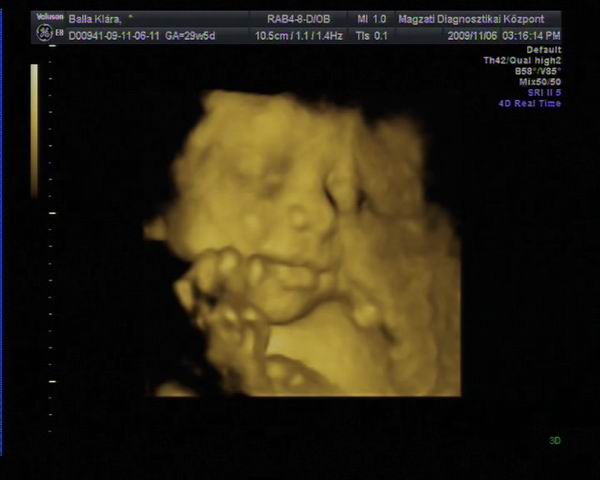

Athena, Jutka. Nilszi-nek igaza van abban, hogy sokszor nem mérnek pontosan az UH-k alkalmával. Misem bizonyítja ezt jobban , mint az én esetem. Szerdán este a rendeléses Uh-n , ahol elég lelkiismeretesen mért a szonográfusnő, ott a picur méretét: 1518g-ra becsülték ( kicsit meg is ijedtem!) A pocakja szép nagy volt AC:255mm a combcsontja, amire kétszer is rámért FL:53mm, BPD( fejátmérő):75mm HC ( fejkörfogat):266mm.

Másnap reggel mentem 4D UH-ra, ahol BPD: 72,6mm HC: 261,9mm AC: 220,2mm FL: 57,5mm becsült súly: 1108g.

Pedig ugyan arról a gyerekről van szó!!!! Nem hiszen, hogy lüktetne a pocakomban. :lol:

Hát ennyit a gépekről és a pontos méretekről!!!

Ráadásul képzeljétek hogy jártam a 4D UH-n. Zsomborka egyáltalán nem akarta megmutatni magát, nem fordult be a gerincem felé néz és annyira betakarta a karjával és a felhúzott lábacskáival magát, hogy semmit nem lehetett látni belőle. Hiába forogtam, mozgattuk a pocakom, fel sem ébredt és egyáltalán nem akart elmozdulni.

Egyetlen képet tudott csak készíteni a szonográfus, azt is csak a talpacskájáról. Nagyon csalódott voltam, mert ugye azt már tudtam, hogy egészséges nincs semmi baja, mert azt már előző nap megnézték, most csak őt szerettük volna látni. Így nagy nehezen kikönyörögtem, hogy nem jöhetnék-e vissza, hátha fordul egy kicsit. Kora délutánra kaptam még egy időpontot. Persze mondanom sem kell, hogy otthon még bukfenceztem is, hogy egy kicsit elforduljon, csokit ettem, kávét ittam ( pedig soha nem iszom )

A babóca mégsem akart elmozdulni, már majdnem azt mondta a szonográfus, hogy csinál egy képet, de hagyjuk a DVD-t mert most sem látszik semmi, mikor egyszer csak mintha halotta volna Zsimbi mégiscsak fordult egy kicsit, hogy végre szülei megcsodálhassák. Persze a kép szemcsés volt és még így is betakart a kis kezecskéje egy kicsit, de mi olyan boldogok voltunk, hogy végre látunk belőle valamit, hogy madarat lehetett volna fogatni velünk. Sőt még ásított is egyet, biztos érezte, mekkora a sikere, annak, ha kicsit produkálja magát. Így végre meg lett a várva várt DVD. Sajnos képet nem tudok róla berakni, mert a laptop-om nem szereti ezt a DVD-t és nem akarja elindítani, így csak a lejátszónkon tudom megnézni, de ott nem tudok képeket kivágni. Így csak egy képet tudok bescannel-ni, amit az Uh-osok nyomtattak ki fekete fehérben.

Nóra

Kép

fikuszka

Kép Zsomborka 28+4